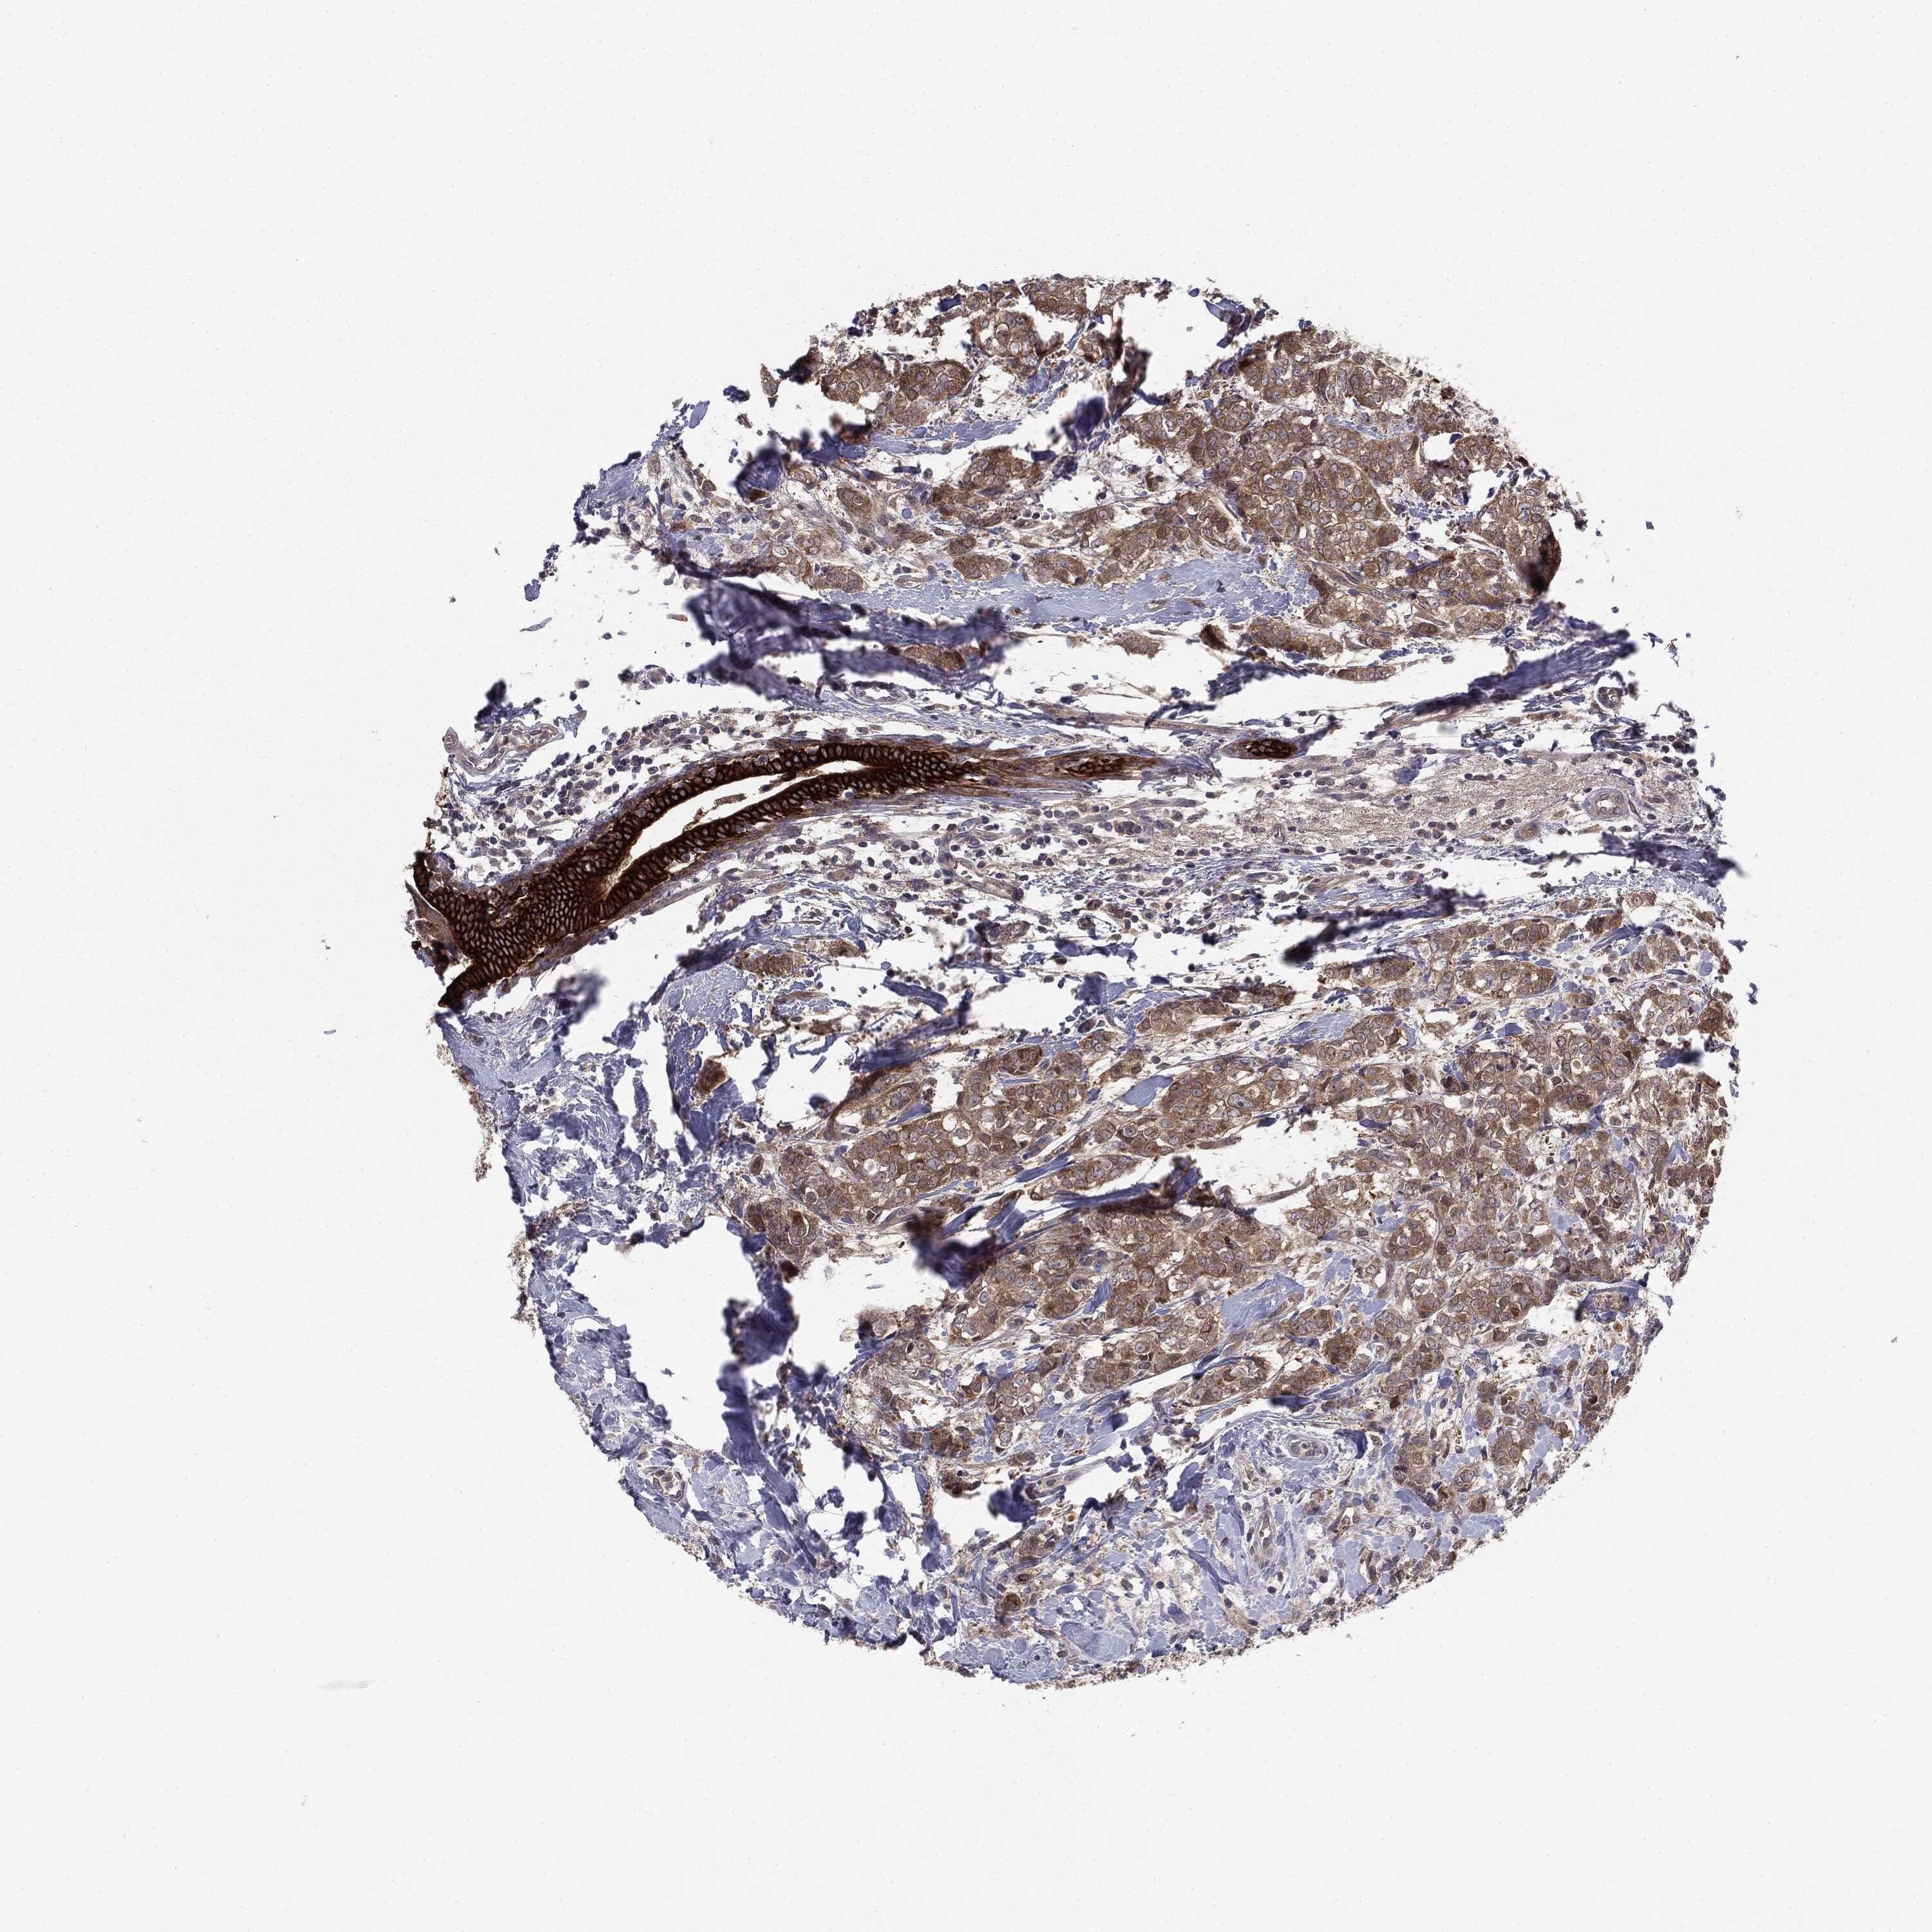

BRCA TCGA BRCA VALIDATION PROTEIN EXPRESSION